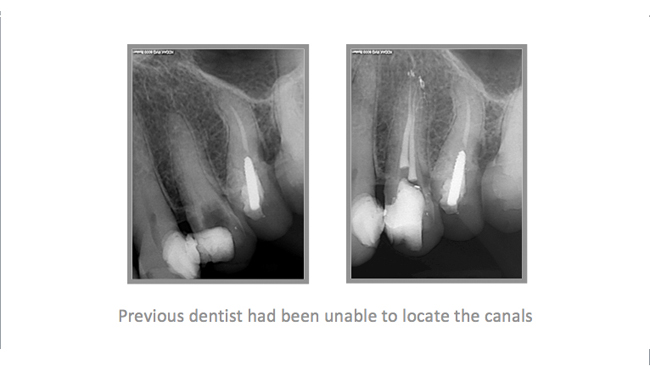

• A few Teeth Treated by Dr. Katsarsky